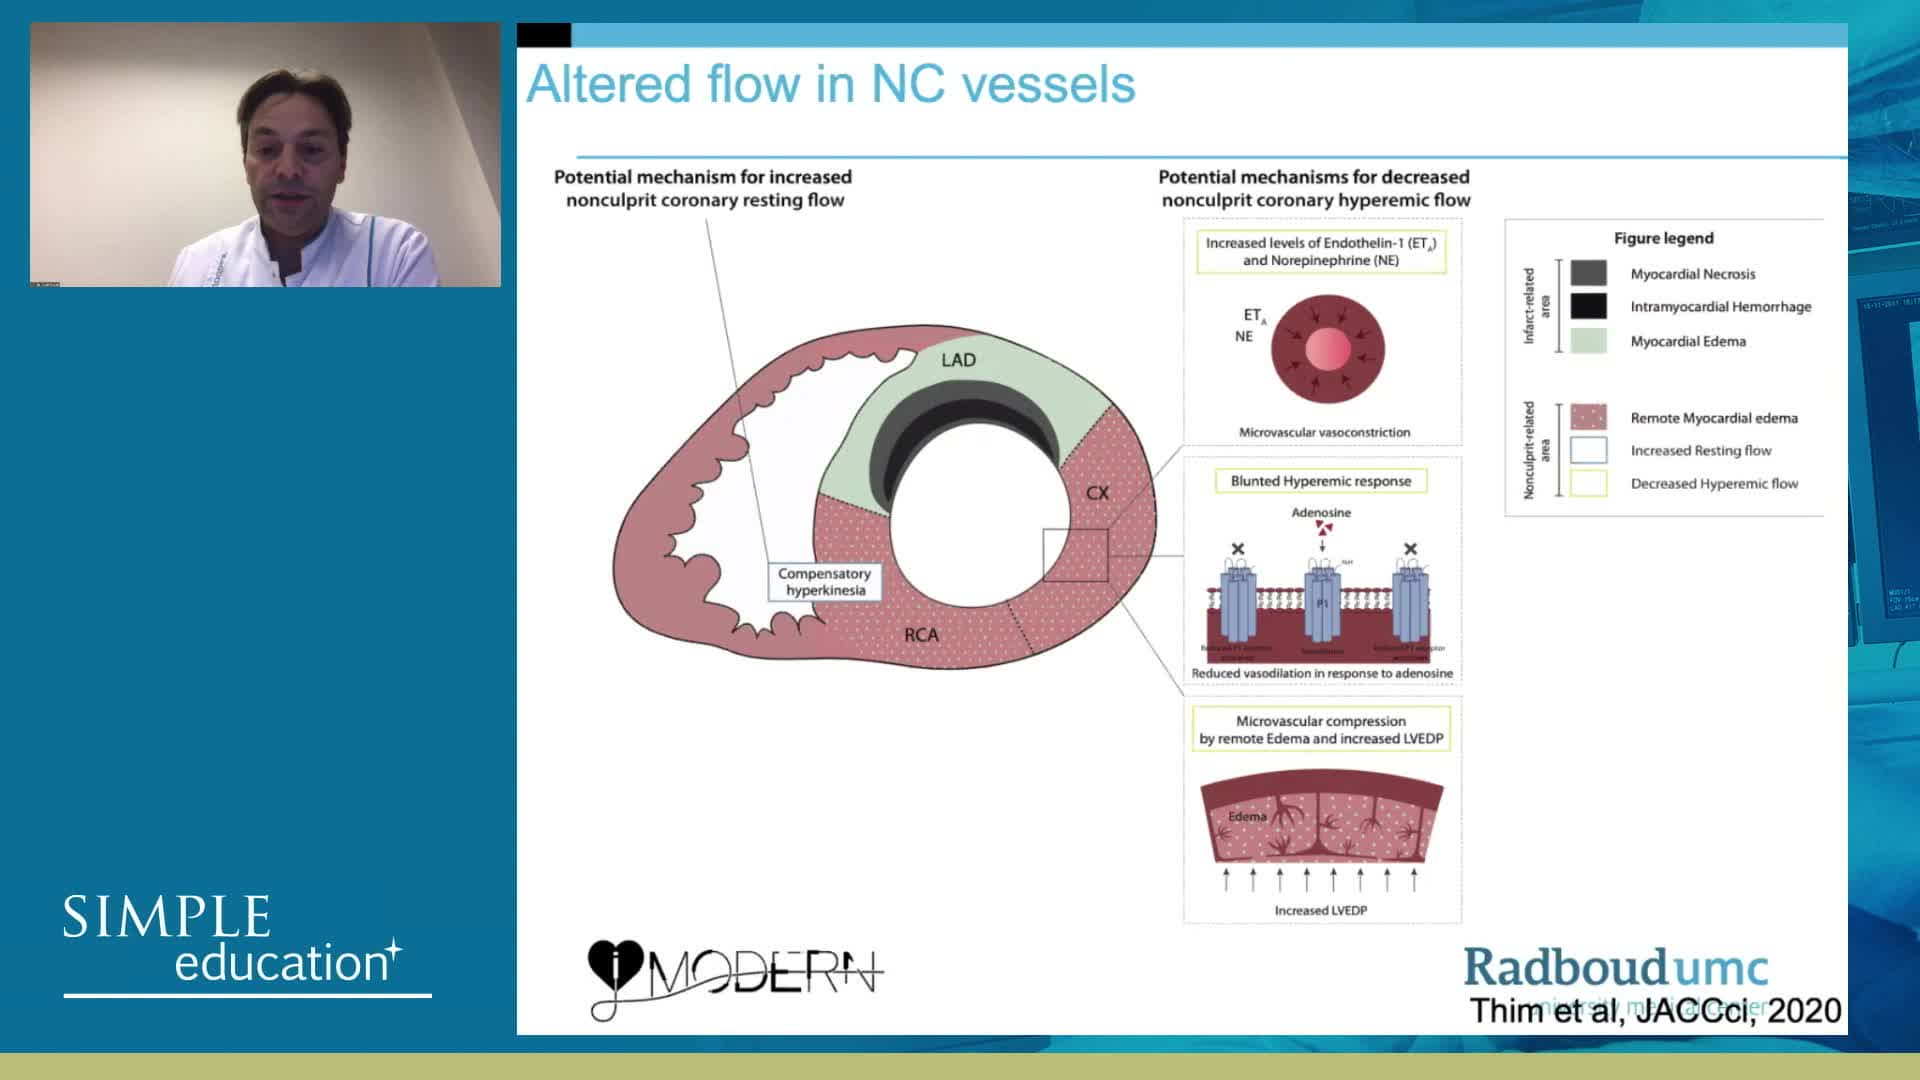

Why is the physiology negative? Integration of the coronary microcirculation to decision-making

Understanding mechanisms of regulation of resting and hyperaemic blood flow, across single and serial stenoses